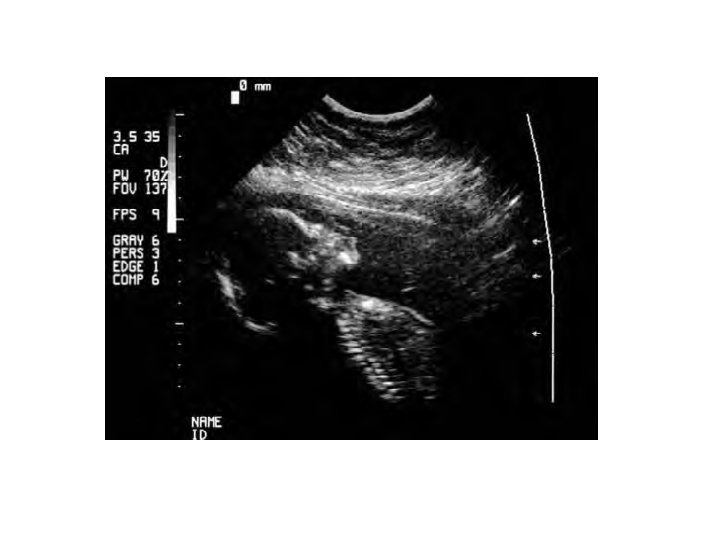

prenatal diagnosis: Ultrasonography Some genetic conditions can be detected through direct visualization of the fetus. § Such visualization is most commonly done with the use of ultrasonography— usually referred to as ultrasound. § In this technique, high-frequency sound is beamed into the uterus; when the sound waves encounter dense tissue, they bounce back and are transformed into a picture. § The size of the fetus can be determined, as can genetic conditions such as neural-tube defects (defects in the development of the spinal column and the skull) and skeletal abnormalities.

1. First, ultrasonography is used to locate the position of the fetus in the uterus. 2. Next, a long, sterile needle is inserted through the abdominal wall into the amniotic sac, and a small amount of amniotic fluid is withdrawn through the needle. 3. Fetal cells are separated from the amniotic fluid and placed in a culture medium that stimulates them to grow and divide. 4. Genetic tests are then performed on the cultured cells. Complications with amniocentesis (mostly miscarriage) are uncommon, arising in only about 1 in 400 procedures.

Chorionic villus sampling (CVS) can be performed earlier (between the 10 th and 12 th weeks of pregnancy) and collects a larger amount of fetal tissue, which eliminates the necessity of culturing the cells. 1. In CVS, a catheter—a soft plastic tube—is inserted into the vagina 2. and, with the use of ultrasonography for guidance, is pushed through the cervix into the uterus. 3. The tip of the tube is placed into contact with the chorion, the outer layer of the placenta. 4. Suction is then applied, and a small piece of the chorion is removed.